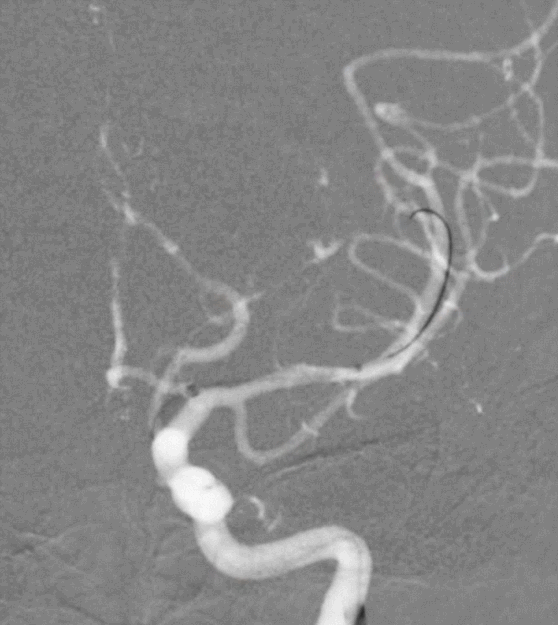

脑血管造影提示右侧颈内动脉颅内段多发动脉瘤(反主动脉弓)

脑血管造影提示右侧颈内动脉颅内段多发动脉瘤

4mm×30mm Streamline

术后4月余随访:多发动脉瘤均未见显影,远端残余轻度狭窄